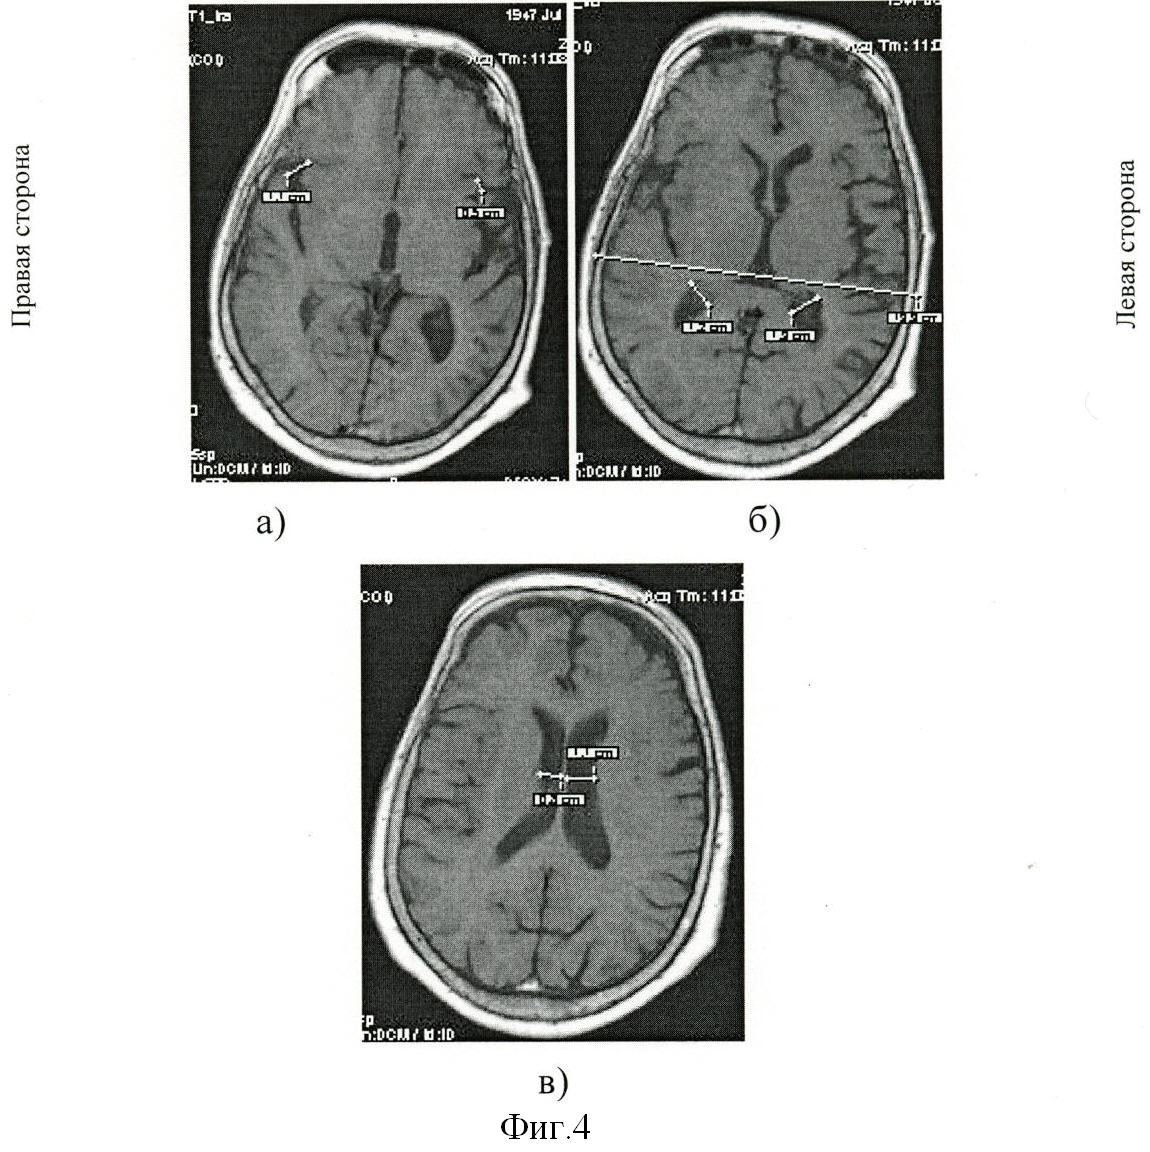

Визуально при магнитно-резонансной томографии выявили: округлая зона (фиг.1а) острого нарушения мозгового кровообращения по ишемическому типу в области таламуса слева размером 2,4×1,4×2,2 см; постишемическая клиновидная киста (фиг.1б) в субкортикальных отделах теменно-височно-затылочной области справа размером 7,3×4,6×6,1 см и множественные мелкие постишемические очаги (фиг.1в) в белом веществе субкортикальных и перивентрикулярных отделов лобных, теменных долей размерами до 0,8 см. Определили наличие смешанной заместительной гидроцефалии. Отметили многоочаговость и асимметричность поражения церебральных структур с локализацией очагов как в базальных отделах, так и субкортикальных зонах обоих полушарий мозга.

С экрана дисплея вычислили реальные величины линейных параметров на трех последовательных срезах, начиная с уровня базальных ганглиев, таламуса и выше. На уровне базальных ядер таламуса определили максимальную ширину сильвиевых борозд справа (20 мм) на фиг.2а и слева (14 мм) на фиг.2а; на уровне визуализации сосудистых сплетений желудочков головного мозга – ширину задних рогов боковых желудочков справа (15 мм) на фиг.2б и слева (12 мм) на фиг.2б и максимальное расстояние между внутренними пластинками костей черепа (150 мм) на фиг.2б; на уровне центральных частей боковых желудочков – минимальную ширину правого (14 мм) на фиг.2в и левого (15 мм) на фиг.2в тел боковых желудочков. Дополнительно рассчитали суммарный когнитивный индекс по предложенной формуле: СКИ=(20+14+15+12+14+15)/150=0,6. Сопоставили вычисленный индекс, равный 0,6, с его критическим значением 0,44. Вычисленный индекс выше значения 0,44, значит прогнозируем развитие постинсультной деменции. И действительно, на 21-ые сутки болезни осмотрен психиатром в связи с расстройствами памяти и мышления, затруднениями в выполнении навыков самообслуживания при регрессе неврологической симптоматики до рефлекторного центрального правостороннего гемипареза. Заключение психиатра: признаки сосудистой деменции с грубым нарушением самообслуживания.